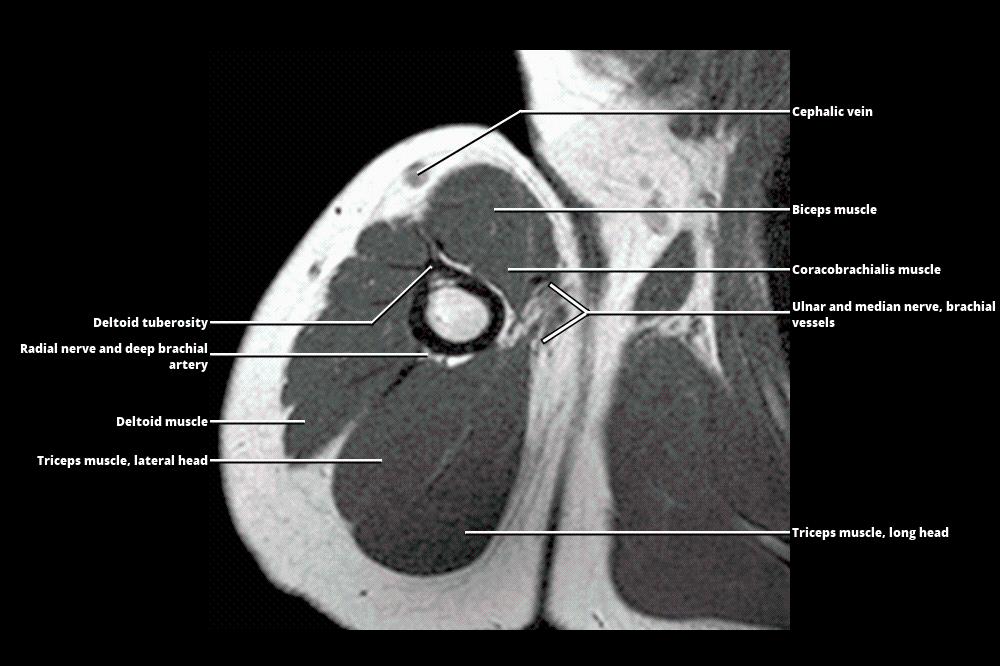

MRI ARM

Upper Arm MRI Anatomy Arm Anatomy Mri Freitasrad is for educational purposes only and should not be used for medical treatment. The first ones help to see if there is an acute muscle injury and analyze which part of the muscle histoarchitecture is injured (balius 2020, peña. An arm mri (magnetic resonance imaging) scan uses strong magnets to create pictures of the upper and lower arm. Musculoskeletal. Arm Anatomy Mri.